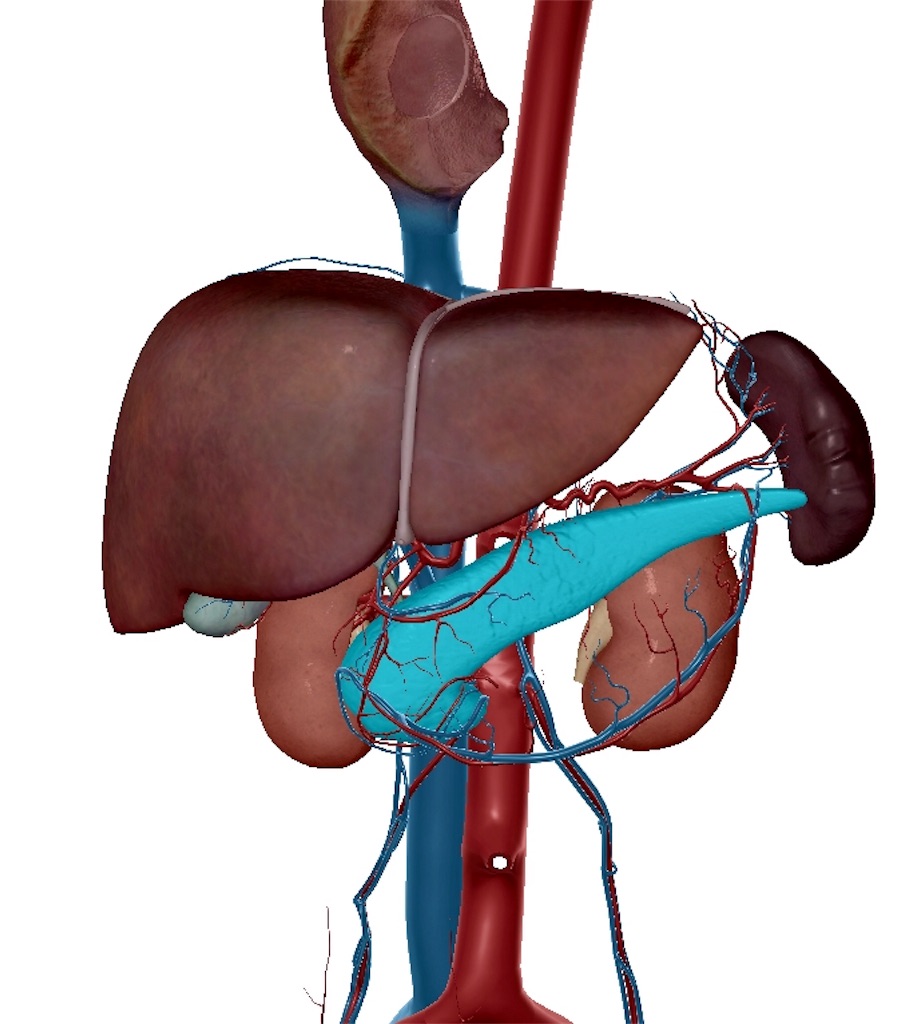

「インスリン作用不足に基づく、慢性高血糖症状を主徴とする代謝疾患群」

この「インスリン作用不足」には2つあります。

・分泌障害

膵臓が疲弊することにより、インスリンを出す能力が低下してしまいます。1型糖尿病に多くなっています。

・インスリン抵抗性

インスリンの受容体の効き目が悪くなり、インスリンが作用できなくなってしまう状態です。